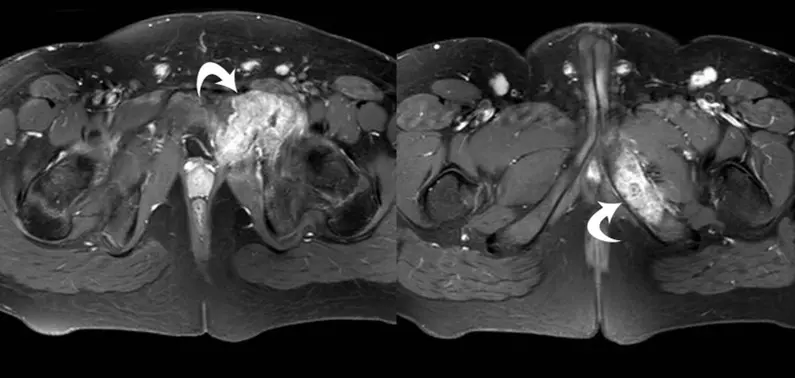

MRI is highly effective for evaluating bone cancer because it precisely shows the length and volume of the tumour, including how far it spreads inside the bone marrow (intramedullary spread) and whether it extends into nearby soft tissues26. This accuracy is crucial for planning limb-sparing surgeries, as MRI measurements of tumour boundaries closely correlate with what is found during surgery, allowing surgeons to determine safe margins for removing the tumour. MRI is also superior to other imaging methods for detecting subtle or early bone lesions, especially when radiographs or CT scans are inconclusive2,4.

In addition to mapping tumour size, MRI can distinguish between cortical destruction and an intact but thinned cortex, which is key for surgical decision-making26. It also shows the tumour’s relationship to important structures, such as nerves, blood vessels, and the joint capsule, helping surgeons avoid critical areas and achieve clear margins. MRI can detect periosteal reactions, such as laminated, sunburst, or Codman triangle patterns, that suggest tumour grade and aggressiveness, with diagnostic performance comparable to conventional radiography21.

MRI further shows soft tissue oedema (swelling) and areas of diffusion restriction (low ADC values), which indicate high tumour cell density and help differentiate malignant from benign lesions27. These imaging features not only guide diagnosis but also allow for monitoring how well the tumour responds to treatments, such as chemotherapy, by tracking changes in marrow signal and the percentage of tumour necrosis2.